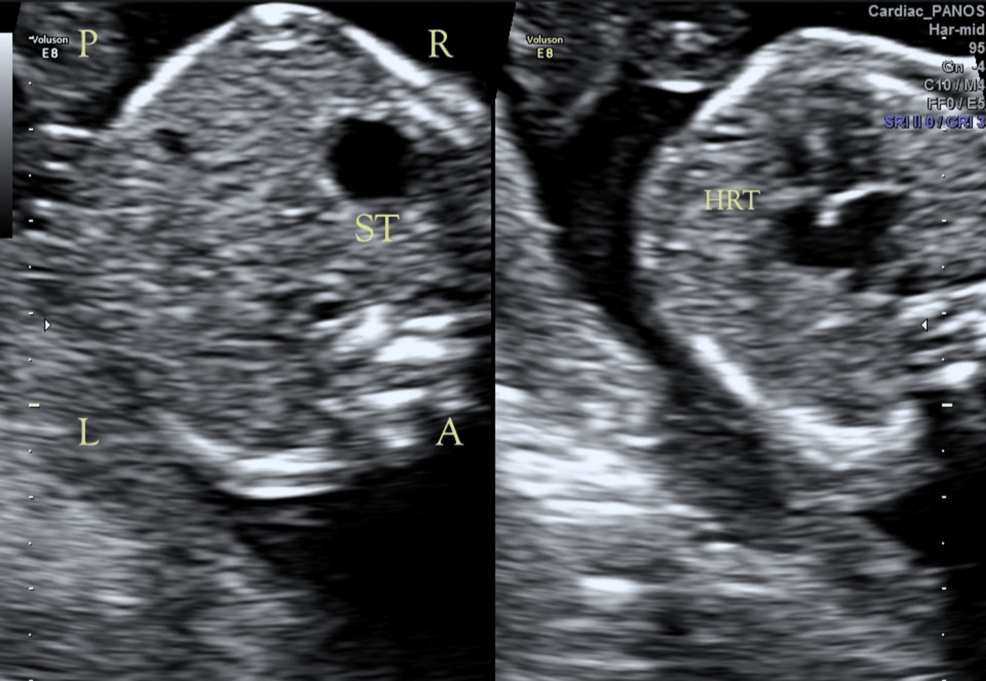

Un reciente informe de caso publicado en Cureus detalla la identificación de variantes genéticas novedosas en el gen CFAP53 en un feto diagnosticado con situs inversus totalis. El situs inversus totalis es una condición rara en la que los órganos internos están dispuestos de forma espejo a su posición normal.

Los investigadores describen el caso de un feto en el que se detectaron variantes heterocigotas compuestas en el gen CFAP53. Este gen está asociado con la función ciliar, que es crucial para el desarrollo embrionario y la determinación de la lateralidad (la disposición izquierda-derecha de los órganos).